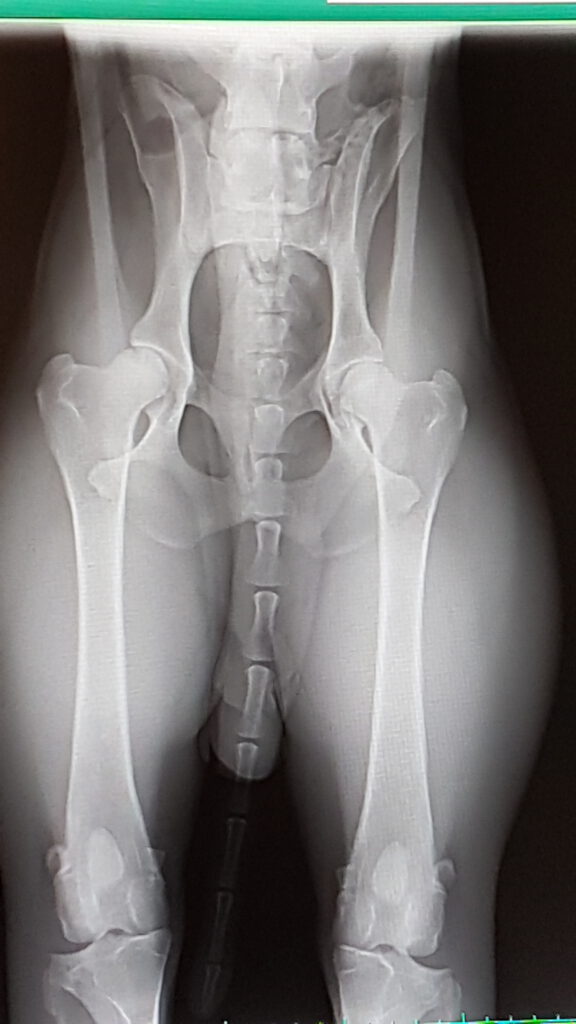

Allgemein Erstes HD-Ergebnis des K-Wurfes von ilona|Veröffentlicht am 29. Juni 2020 Alles sehr gut – Knox hat den HD-Wert A2 und ED/OCD frei – was will man mehr! Danke an´s Praxisteam Dr. Wolf, Creußen – Foto vom Bildschirm geschossen Wir haben uns gefreut – alles im „grünen Bereich“